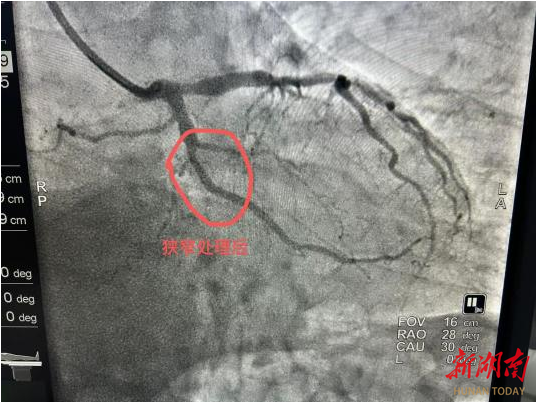

2. 适配特殊病变场景:像影像中这类局限性的血管狭窄,或是支架内再狭窄、小血管病变、分叉病变等情况,药物球囊能精准处理病变部位,避免了复杂病变下支架植入的局限性,也降低了多支架叠加的风险。

从影像看治疗效果:

“打通河道”且不留痕迹

此次治疗的造影对比极具说服力:术前狭窄处血管血流受阻,心肌供血不足,患者可能出现心绞痛等症状;药物球囊扩张后,狭窄处血管恢复正常管腔形态,血流顺畅通过,心肌缺血问题得到解决。更重要的是,血管内没有支架的“占位”,保留了血管的生理结构,为未来可能的再次治疗预留了更多空间。